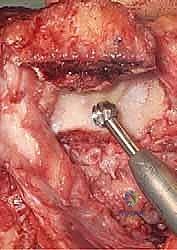

2. الشق الجراحي وحماية الأعصاب

يقوم الدكتور هطيف بعمل شق طولي خلف الكوع. الخطوة الأكثر أهمية هنا هي تحديد العصب الزندي (Ulnar Nerve) وعزله وحمايته بعناية فائقة باستخدام تقنيات الجراحة الميكروسكوبية الدقيقة لتجنب أي تلف قد يؤدي إلى ضعف في اليد.

3. إزالة العظام المحطمة وتحضير القناة العظمية

بمجرد الوصول إلى المفصل، يتم تقييم حجم الدمار. تُزال الشظايا العظمية المفتتة التي لا يمكن إنقاذها. بعد ذلك، يتم تحضير القناة الداخلية لعظم العضد (من الأعلى) وعظم الزند (من الأسفل) باستخدام أدوات قياس دقيقة جداً لضمان تطابق المفصل الصناعي مع تشريح المريض.